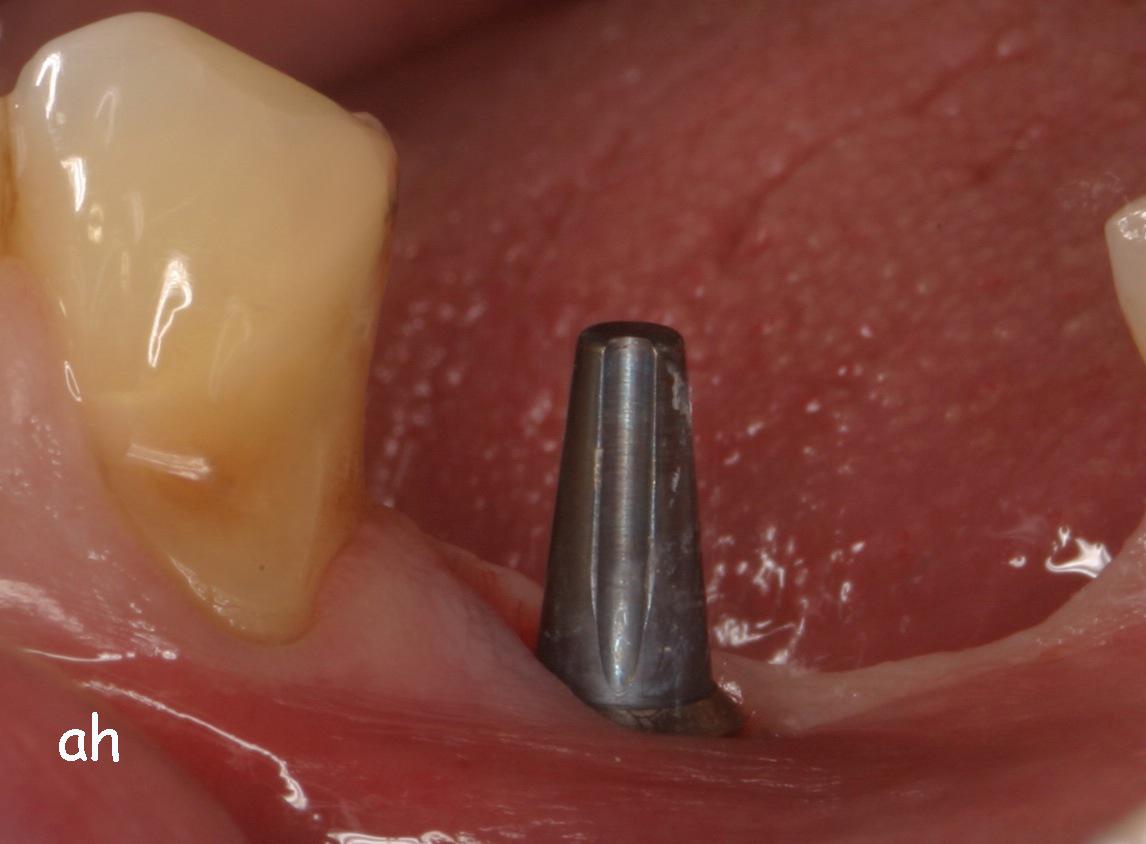

Exemple 7: Un implant au niveau de la deuxième prémolaire inférieure gauche.

Exemple 7: Le moignon vissé sur l'implant.